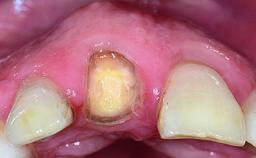

A 32-year-old female Caucasian patient with a compromised maxillary right central incisor was referred to us by a general dentist. Her chief complaints were discomfort and mobility of tooth 11 with unsatisfactory esthetics due to discoloration. The patient reported a previous trauma, some years earlier, as the origin of pathology on the afflicted tooth. Anamnesis was negative for any other dental or periodontal pathology in the remaining dentition. The patient did not take any medication and reported to be a light smoker (5–10 cigs/day). She had high esthetic expectations of her treatment. The extraoral examination revealed a high smile line with full exposure of her maxillary teeth and surrounding soft tissue in the area between the second premolars.

Soft Tissue Anatomy Intact Defective

Bone Volume Horizontally and vertically sufficient Horizontally deficient Deficient vertically or deficient vertically AND horizontally

Bone Volume Deficient horizontally, requiring prior grafting

Soft Tissue Contour and Volume Slightly compromised